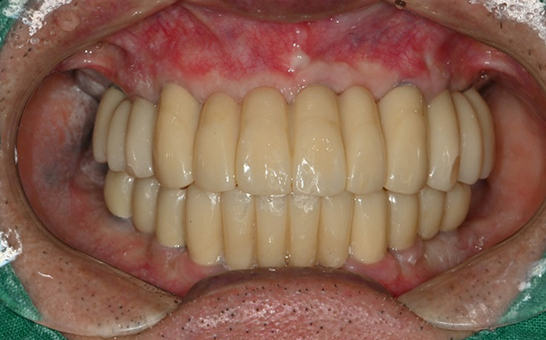

바른선택치과의원 전악 임플란트

치료 시작 전 촬영 2024.01.24 | 치료 완료 후 촬영 2024.12.26

CASE 01 김** / 60대

전악임플란트

1 예후불량 치아 발치

2 발치 후 즉시 임플란트 식립 및 뼈이식

3 고정성 보철물로 수복 후 일상 회복